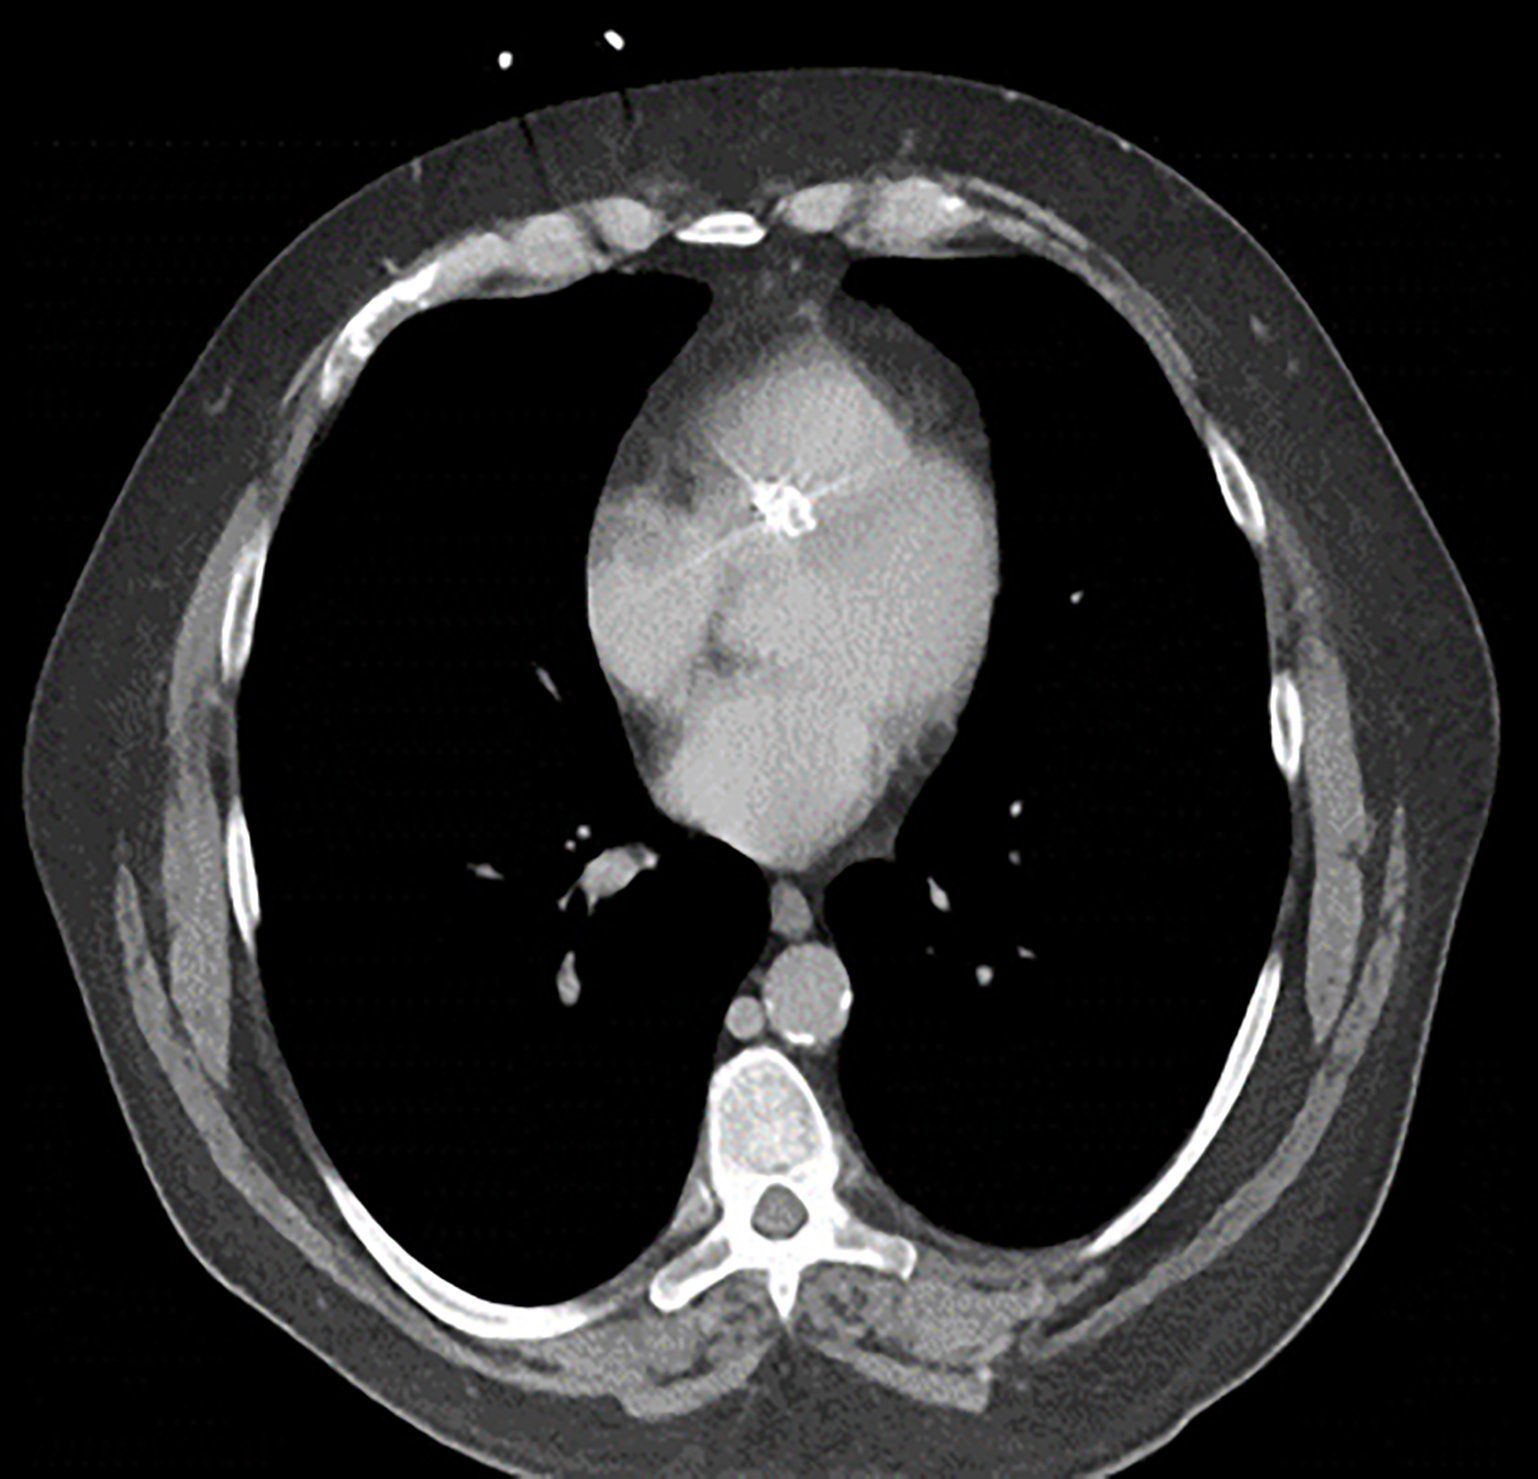

Endovascular coil embolization continues to become a more frequent modality of addressing hemorrhage and bleeding in patients. Migration refers to the coil unraveling or moving from the original embolization site. Migration of a coil is a known complication which can lead to serious consequences based on where the coil migrates. Despite increasing efforts to improve safety and technique, the risk of migration remains. We present a case of an embolization coil that migrated to the right ventricle, which was incidentally found roughly 2 months after undergoing an interventional radiology procedure for gastric variceal bleeding. The patient presented to the emergency department with dyspnea and abdominal pain. Unique images were obtained during his visit and in subsequent follow-up. As use of vascular embolization coils continues to become more commonplace, understanding the risks and complications of these procedures remains an important aspect of providing care for patients once they have left the interventional radiology suite. Coil migration should be a differential to consider in patients who present to the emergency department with signs or symptoms of arrhythmia or pulmonary embolism who have undergone a coil embolization procedure.